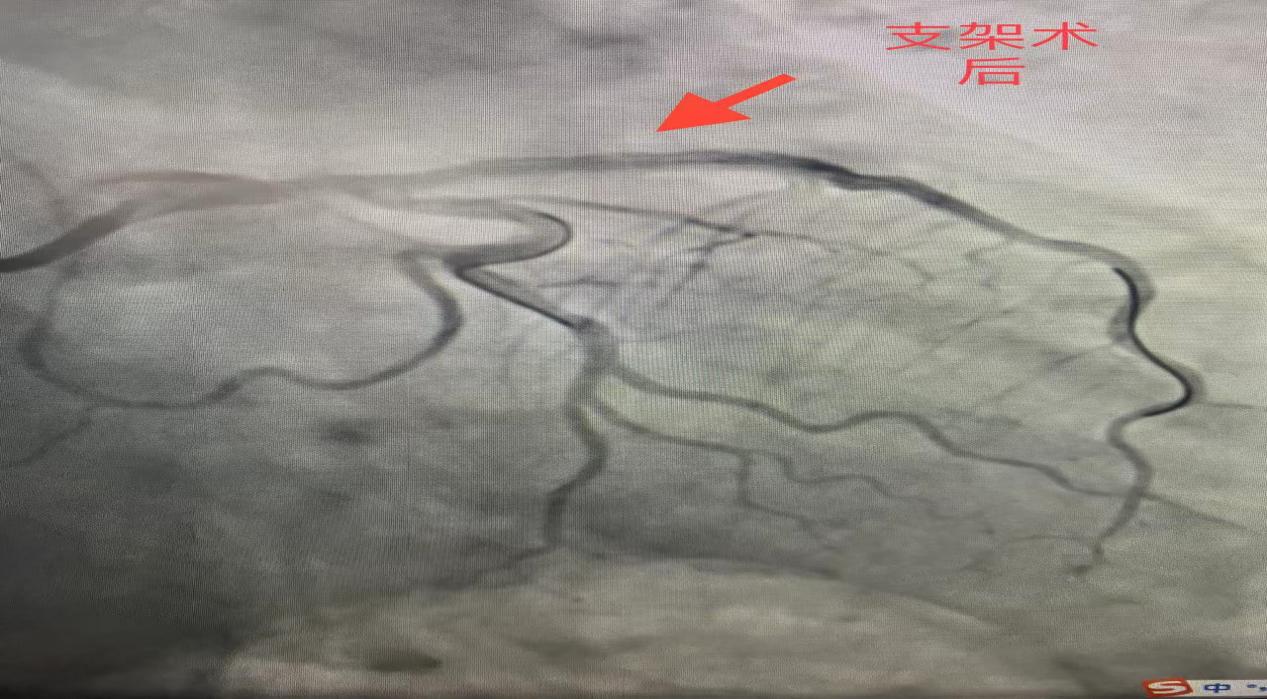

随后,依托医共体高效转诊机制,患者被迅速转运至安陆市普爱医院,并直接进入导管室完成冠脉介入治疗,血管顺利开通。术后患者生命体征平稳,转入CCU康复。